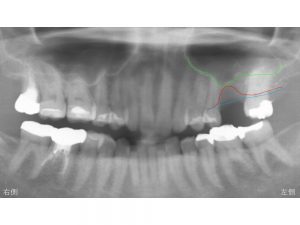

上顎左側奥から2番目が欠損しています。

現在の骨の状態を赤線で記載します。

骨が最も吸収している位置です。

元々の骨の位置は以下の青線です。

ここまで骨があったのです。

次の線は上顎洞という位置です。

以下の緑線が上顎洞の底の位置です。

上記の3つの線を合わせたのが以下です。

赤線と緑線の間に骨が存在します。

もし、骨吸収せずに青線まで骨があれば

青線から緑線までの間が骨ですから

十分な骨の高さがあります。

しかし、現状では赤線まで骨吸収しているわけですから

かなり骨の高さが少ないことがわかります。